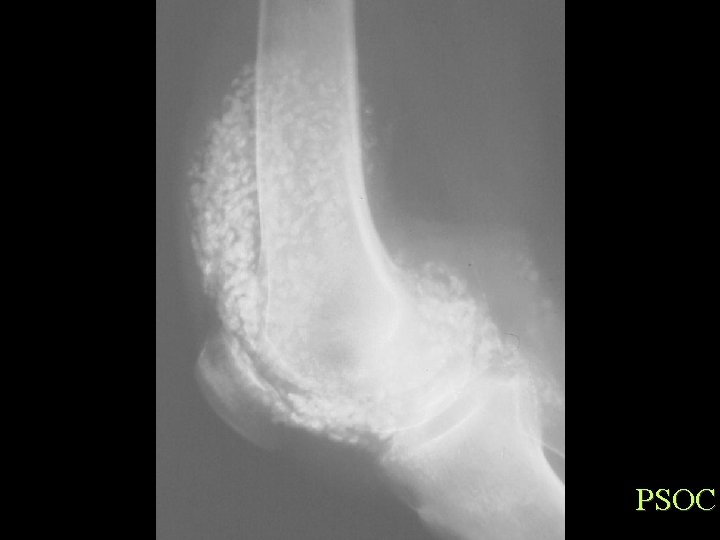

Soft Tissue Calcification By Cause Generalized Calcinosis Idiopathic Tumoral Calcinosis • • 10 -30 Yrs, black Elevated phosphate Single or multiple firm tumour like painless Hips, Shoulders, Elbows, Ankles Dense, Flocculent, Amorphous, 1 -20 cm, fluid levels Dx of exclusion

ITC

Calcification By Shape Tumoral calcinosis DDX • • • Idiopathic Renal osteodystrophy Gout Hypervitaminosis D Hyperparathyroidism Collagen vascular Disease

PSOC